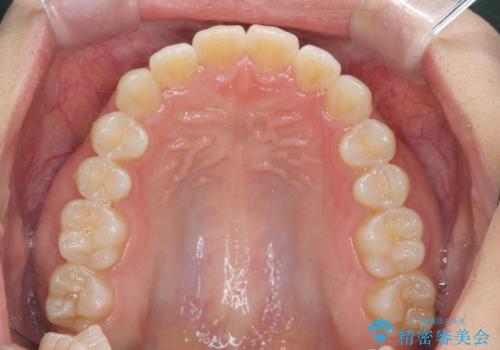

前歯のすれ違い インビザラインで行うマウスピース矯正

- 前歯のガタつき、でこぼこ、前後が逆になっている噛み合わせの改善を求めて来院されました。

治療の装置が目立たず歯ブラシのしやすいマウスピース矯正インビザラインでの治療を計画します。

20時間/日の装用時間をしっかりと守っていただき、きれいな歯並びを手に入れることができました。